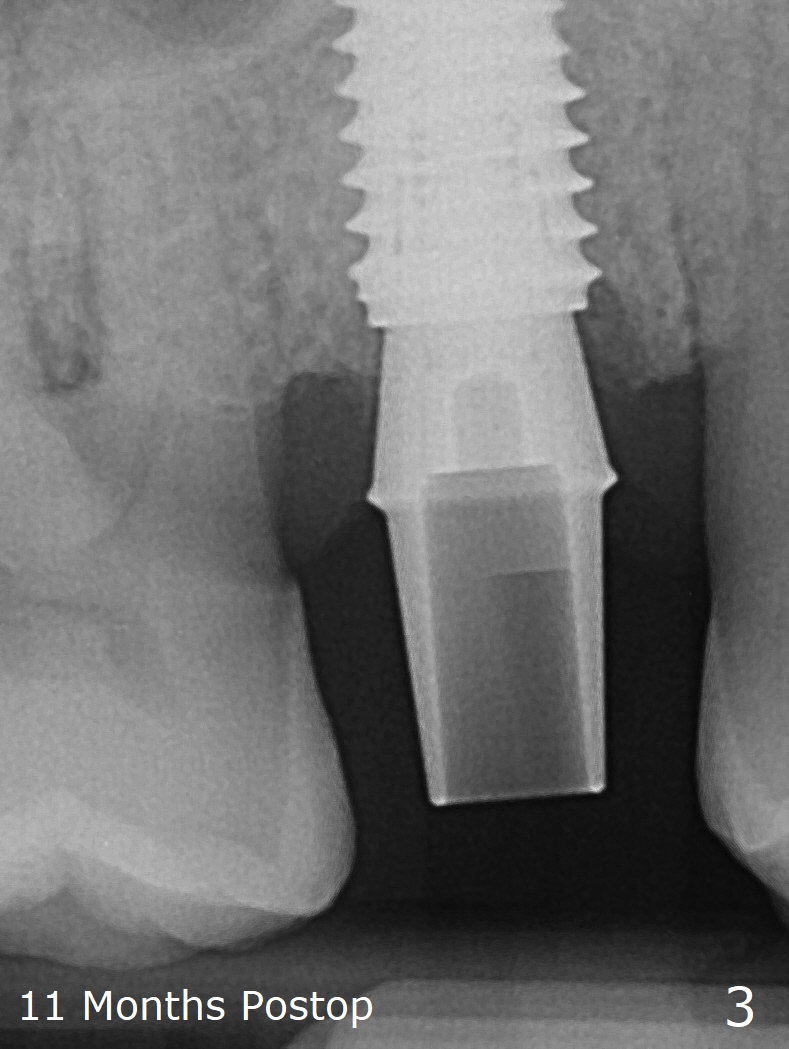

In fact the designed initial drills do not get to the bone with guides. After use of the next length drills (1.5 mm longer with sharp end), the sinus floor perforates without membrane perforation. Once 3.5 mm drill is used following sequential osteotomy, a 4x10 mm dummy implant is placed for sinus lift with 1 mm short of the depth and >50 Ncm. Following the dummy implant removal, allograft in the amount of 2 to 3 amalgam carriers is delivered for sinus lift (Fig.1,2 white *), followed by implant placement (4.5x10 mm, >55 Ncm). More allograft is placed before and after abutment insertion (black *). As usual, an immediate provisional is fabricated at each site. After removal and cleaning, the abutments are reseated and retorqued to 30 Ncm 11 months postop (Fig.3,4). Sinus lift is indistinct 15 months postop (Fig.5,6), probably due to radiation overexposure, although placement trajectory is good.